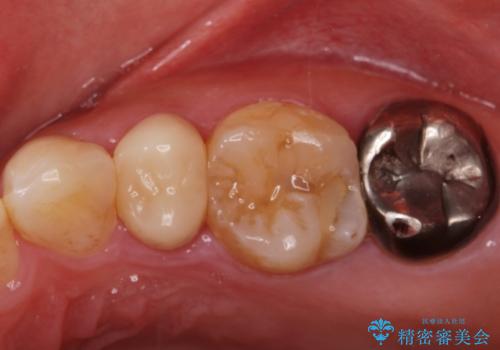

- 他院で被せた保険の白い被せ物(樹脂)をセラミックの被せ物に変えたいとの事で来院。

被せ物を外し、虫歯がないことを確認してセラミックの被せ物(ジルコニアクラウン)の治療を行いました。